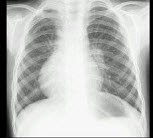

16、问答题 肺不张的X线表现有哪些?

男,12岁,平时无明显不适,结合图像,最可能的诊断是()

A.正常胸片

B.左旋心

C.右旋心

D.镜面右位心

E.以上都不是